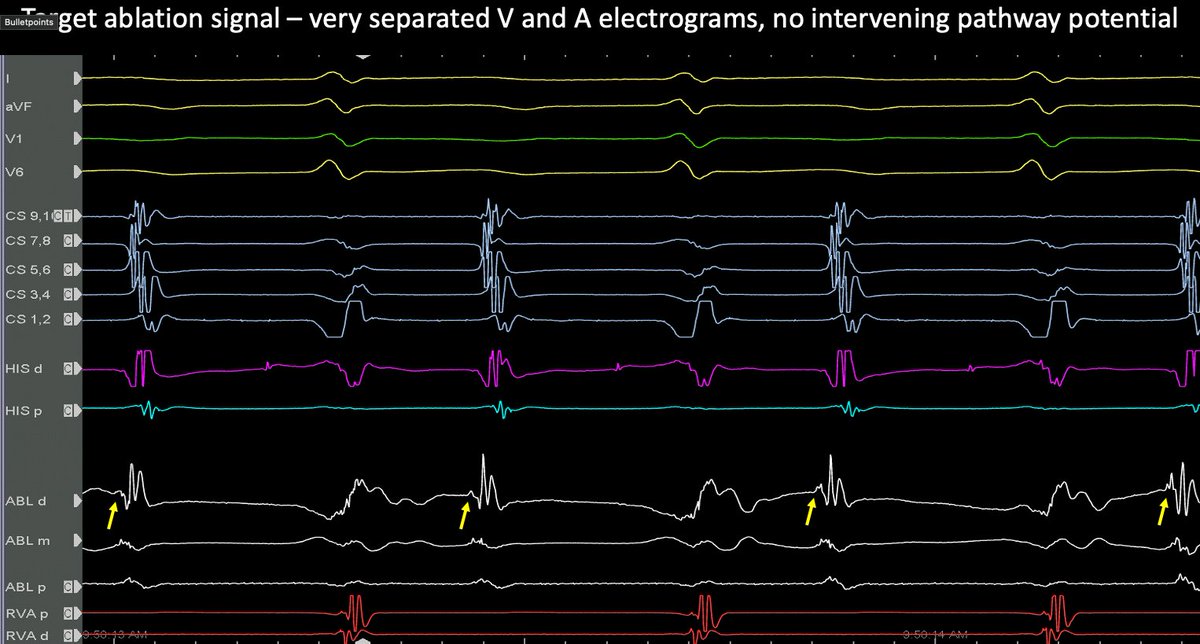

7/ Slow pathway targeted for ablation. 6s of RF was enough to totally remove the two for one responses (TFORs). Post ablation everything normalised. I thought this was a rare but satisfying case. @finnakerstrom

6/ EP study showed helped confirm. There was no VA conduction. Antegrade conduction showed continuous double fire responses without tachycardia. Very hard to systematically do an EP study.